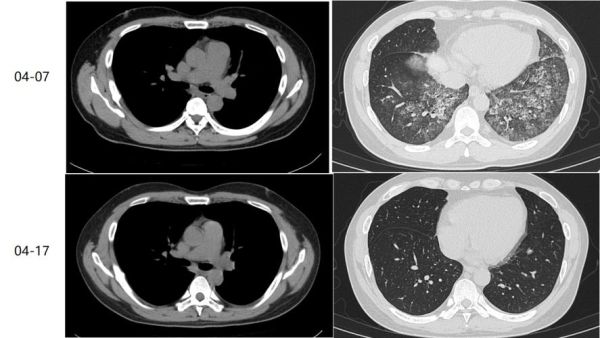

(图片来源网络,侵删)